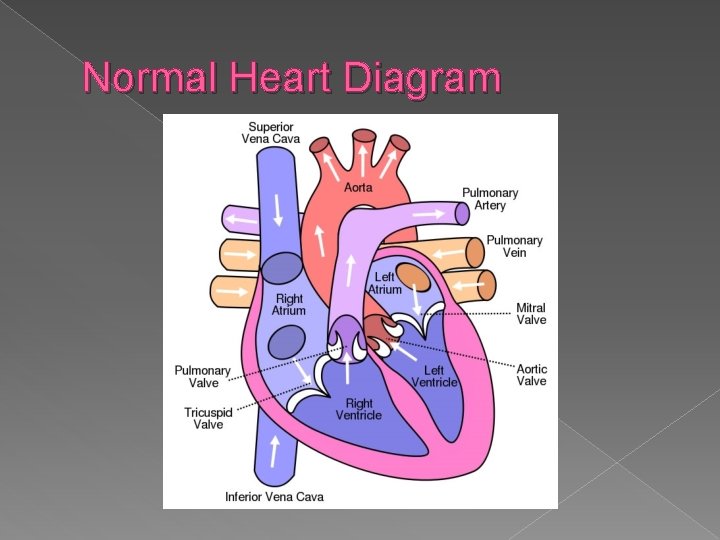

Normal Heart Diagram

� The fetal heart occupies approximately one third of the thoracic cavity.

Fetal circulation Oxygenated blood enters the fetus through the umbilical vein � The ductus venosus partially bypasses the lever to send oxygen – rich blood to the right ventricle � The foramen ovale shunts some of the right atrial blood directly into the left atrium � The ductus arteriosus allows oxygen-rich blood from the pulmonary artery into the aortic arch to circulate throughout the fetus �

� Ductus Venosus: In the fetus, the ductus venosus shunts approximately half of the blood flow of the umbilical vein directly to the inferior vena cava. Thus, it allows oxygenated blood from the placenta to bypass the liver. In conjunction with the other fetal shunts, the foramen ovale and ductus arteriosus, it plays a critical role in shunting oxygenated blood to the fetal brain

� Foramen Ovale: a shunt from the right atrium into the left atrium � Ductus Arteriosus: a shunt connecting the pulmonary artery to the aortic arch. It allows most of the blood from the right ventricle to bypass the fetus's fluid-filled lungs